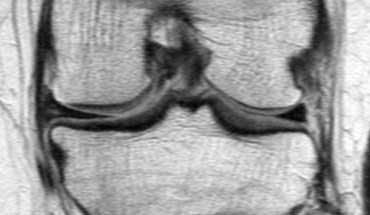

Bên trái là một trường hợp sụn chêm lật khác.

Lần này ở phía trong (medial).

Một phần sừng trước bị lật ra phía sau.

Chỉ một phần nhỏ của sừng trước được nhìn thấy ở phía trước.

Hầu hết các trường hợp sụn chêm lật xảy ra ở phía ngoài (lateral).

Dây chằng chéo trước (ACL) ngăn mảnh sụn chêm di chuyển hoàn toàn vào hố gian lồi cầu.

Trên hình ảnh mặt phẳng coronal, trước tiên sẽ thấy sừng trước to và phồng lên.

Ở phía sau sẽ thấy sừng sau rất nhỏ.